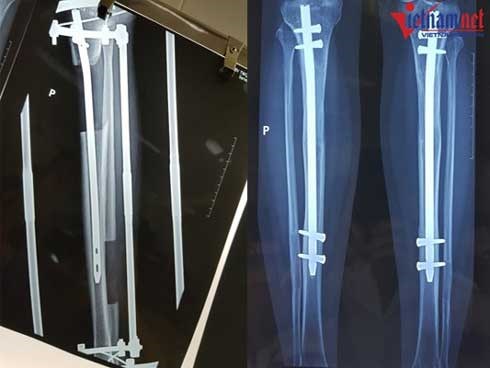

phẫu thuật kéo dài chân

Đau đớn kéo dài chân: "Tôi nghe tiếng đục, khoan, cắt xương trên chính cơ thể mình!"

Cao thêm 7cm Hưng cảm thấy cuộc đời mình đã bước sang trang mới, dù vậy nhớ về quãng thời gian thực hiện thủ thuật, chàng trai 9x vẫn không quên được cảm giác đau đớn còn ám ảnh.

Có thể cao thêm tới 20cm, kéo dài chân đau cỡ nào?

Về nguyên tắc, khi xương dài đến đâu, gân cơ sẽ phát triển đến đó và có thể kéo dài tối đa tới 20cm.